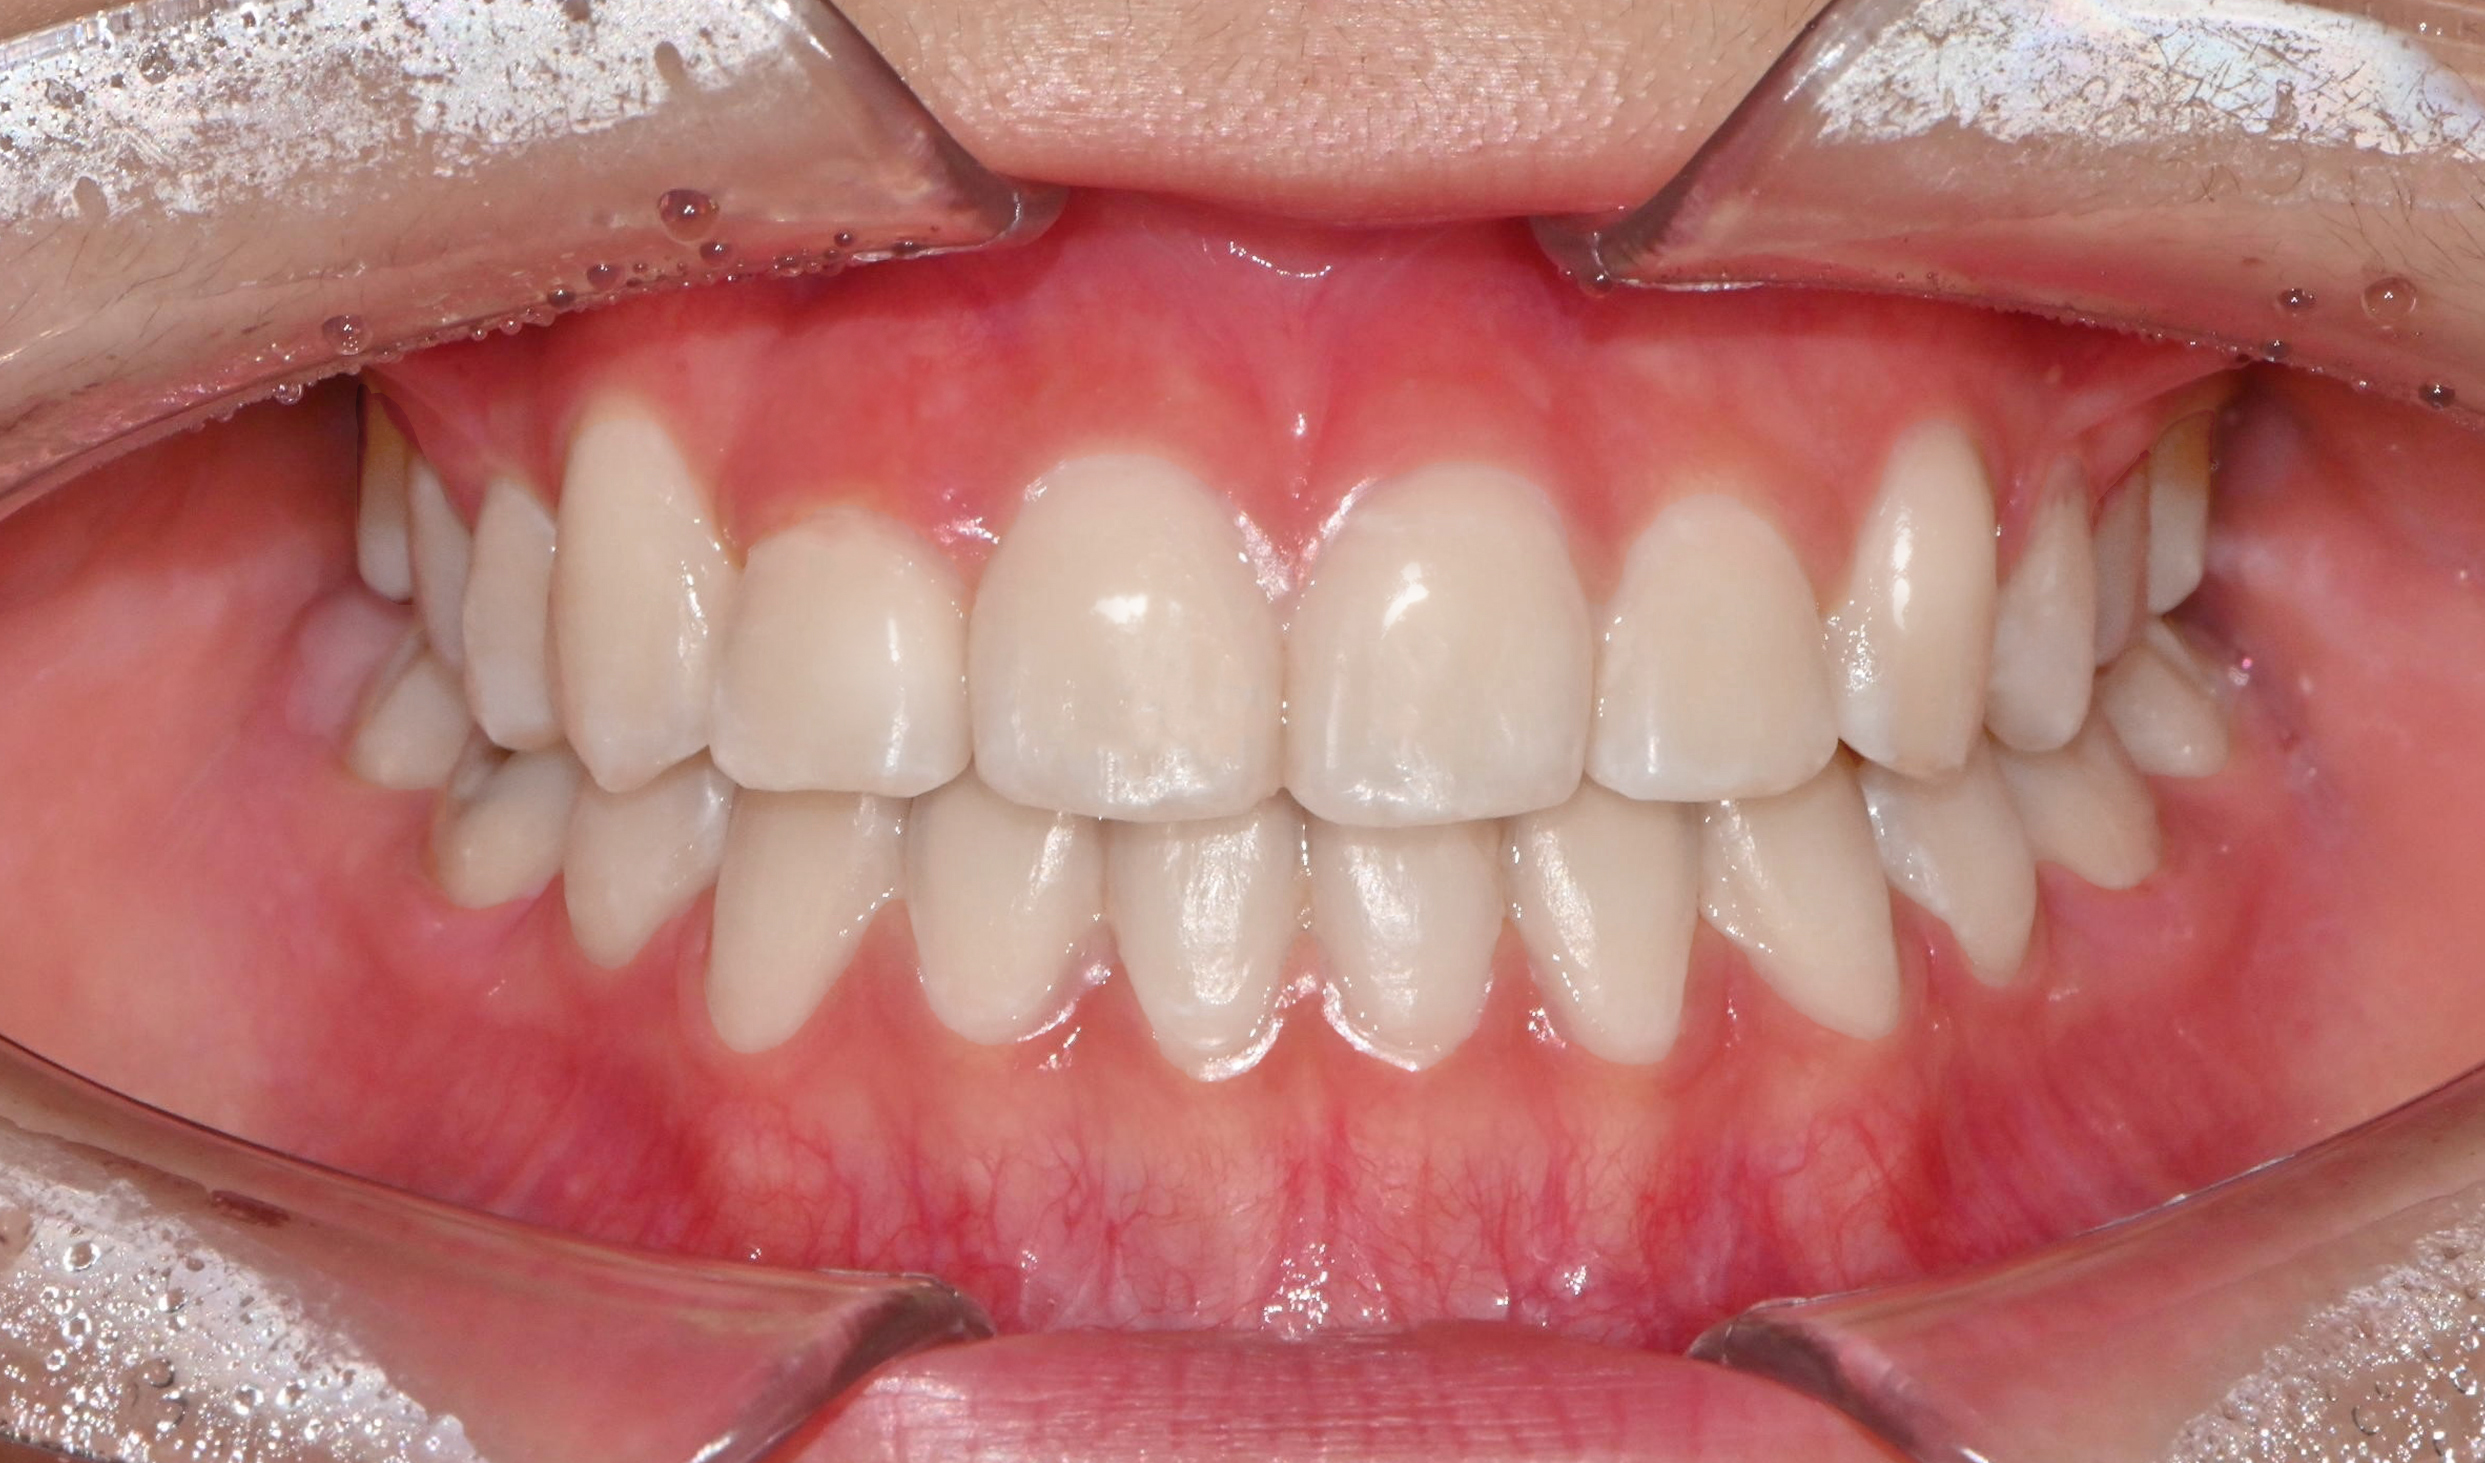

치과가 무서워 10년 동안 미뤄온 임플란트 수술 그 결과는?